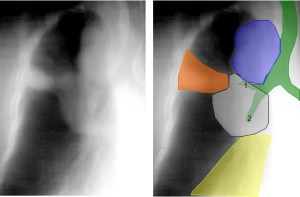

SIGNO DEL ARCO AÓRTICO OCULTO

En la radiografía lateral de tórax, se ha descrito que la ausencia de la imagen del arco aórtico puede ser la clave diagnóstica de coartación aórtica. La imagen izquierda muestra el signo. Se trata del mismo paciente del Signo de las muescas costales (ver Otros signos de pleura/pared). La imagen derecha corresponde a una radiografía normal con la sombra aórtica visible (flecha).

Se han propuesto varias explicaciones para este signo; puede ser debido a hipoplasia del arco aórtico combinada con la coartación, a dilatación de las arterias braquiocefálicas (particularmente la arteria subclavia izquierda) que oscurecen el margen superior del cayado, o a hipoplasia y desplazamiento anteromedial de la porción distal del arco aórtico.

Este artículo de Chen es la referencia: Obscured aortic arch on the lateral view as a sign of coarctation. Radiology 1984: 153; 595-596.